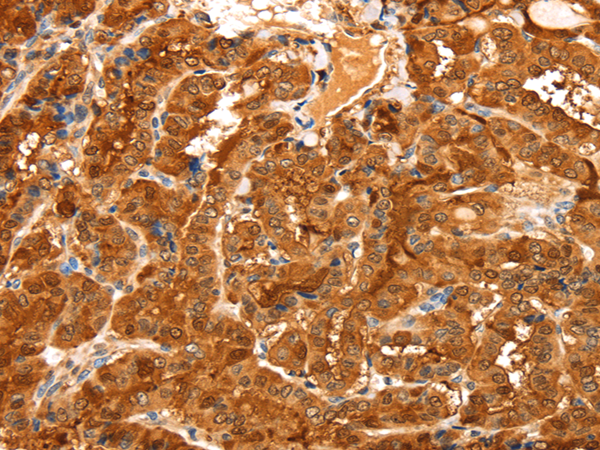

IHC positive control: |

Human thyroid cancer and Human brain |

IHC Recommend dilution: |

50-200 |